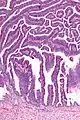

Very high magnification

The name of the lesion describes it microscopic appearance. It has nipple-like structures with fibrovascular cores (papillae) that are long in relation to their width (villus-like), which are covered with a glandular pseudostratified columnar epithelium.